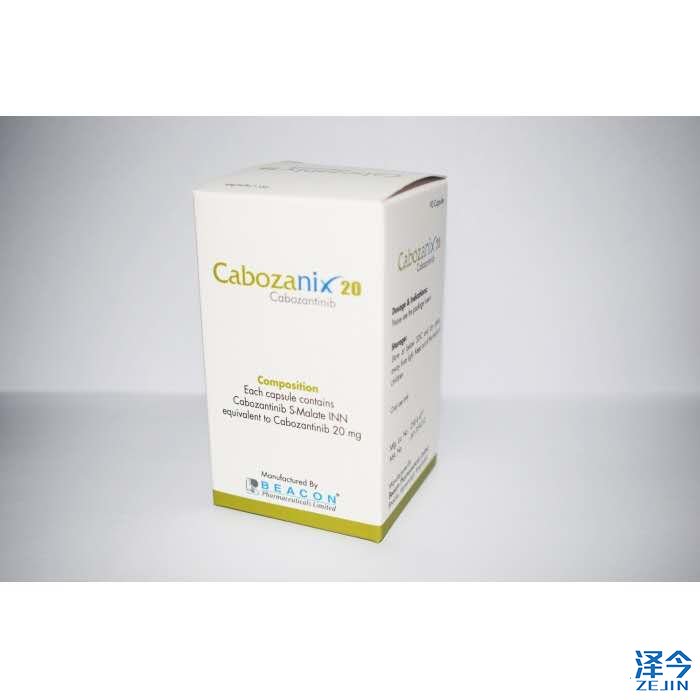

今天重点介绍的是卡博替尼,卡博替尼作为一个在国内没有上市的多靶点靶向药,是肾癌一线用药,肝癌等多个实体肿瘤二线用药,在骨转移领域,有相关数据统计其对肝癌、前列腺癌和卵巢癌骨转移患者的疾病控制率分别可达76%、71%和58%,黑色素瘤、乳腺癌和非小细胞肺癌骨转移的疾病控制率分别为45%、45%和40%。不少患者甚至服药一周即可疼痛感消失,骨转实现彻底缓解。

但是目前卡博替尼在国内尚未上市,据泽今出国医疗透露,截止到目前唯一正规的仿制版是碧康公司今年的推出的,购买者需注意不要买到印度等仿制药的大国的原料假冒品。